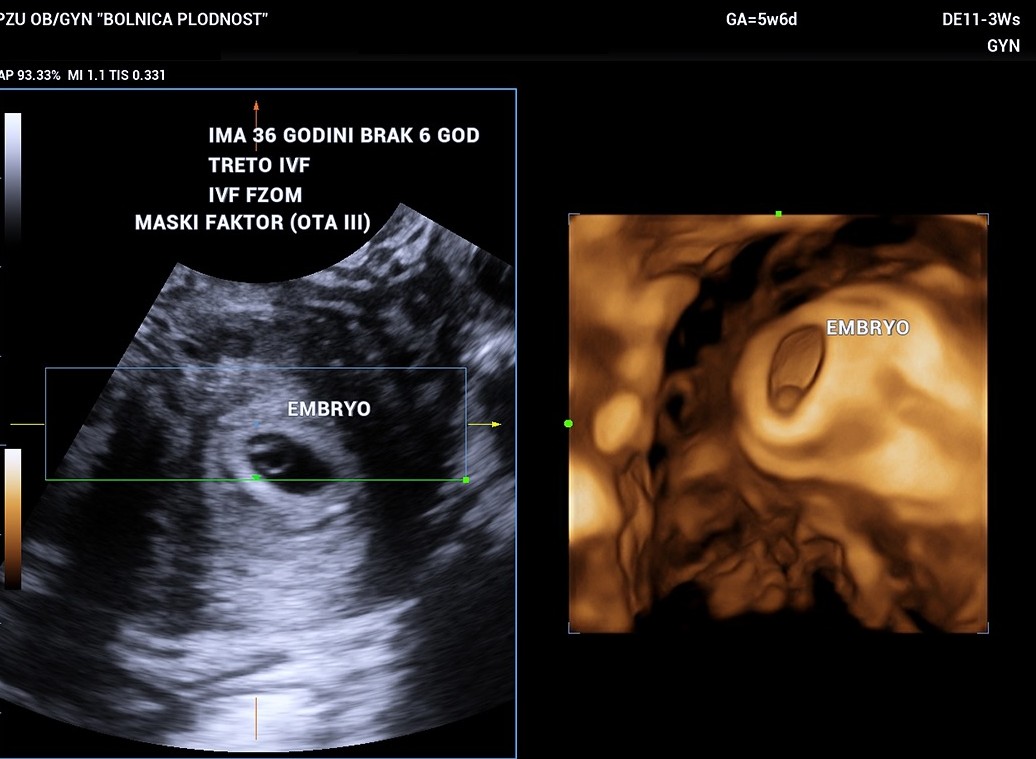

Case 3: 36-Year-Old Patient – Tailored Third IVF Protocol

A 36-year-old patient, previously unsuccessful with two IVF cycles and facing a male factor diagnosis (OTA III), needed a carefully customised approach. After in-depth consultations and using the latest technology, we designed a protocol that suited her hormonal and reproductive profile.

Result: Positive pregnancy test, currently in the 5th gestational week and 6 days.